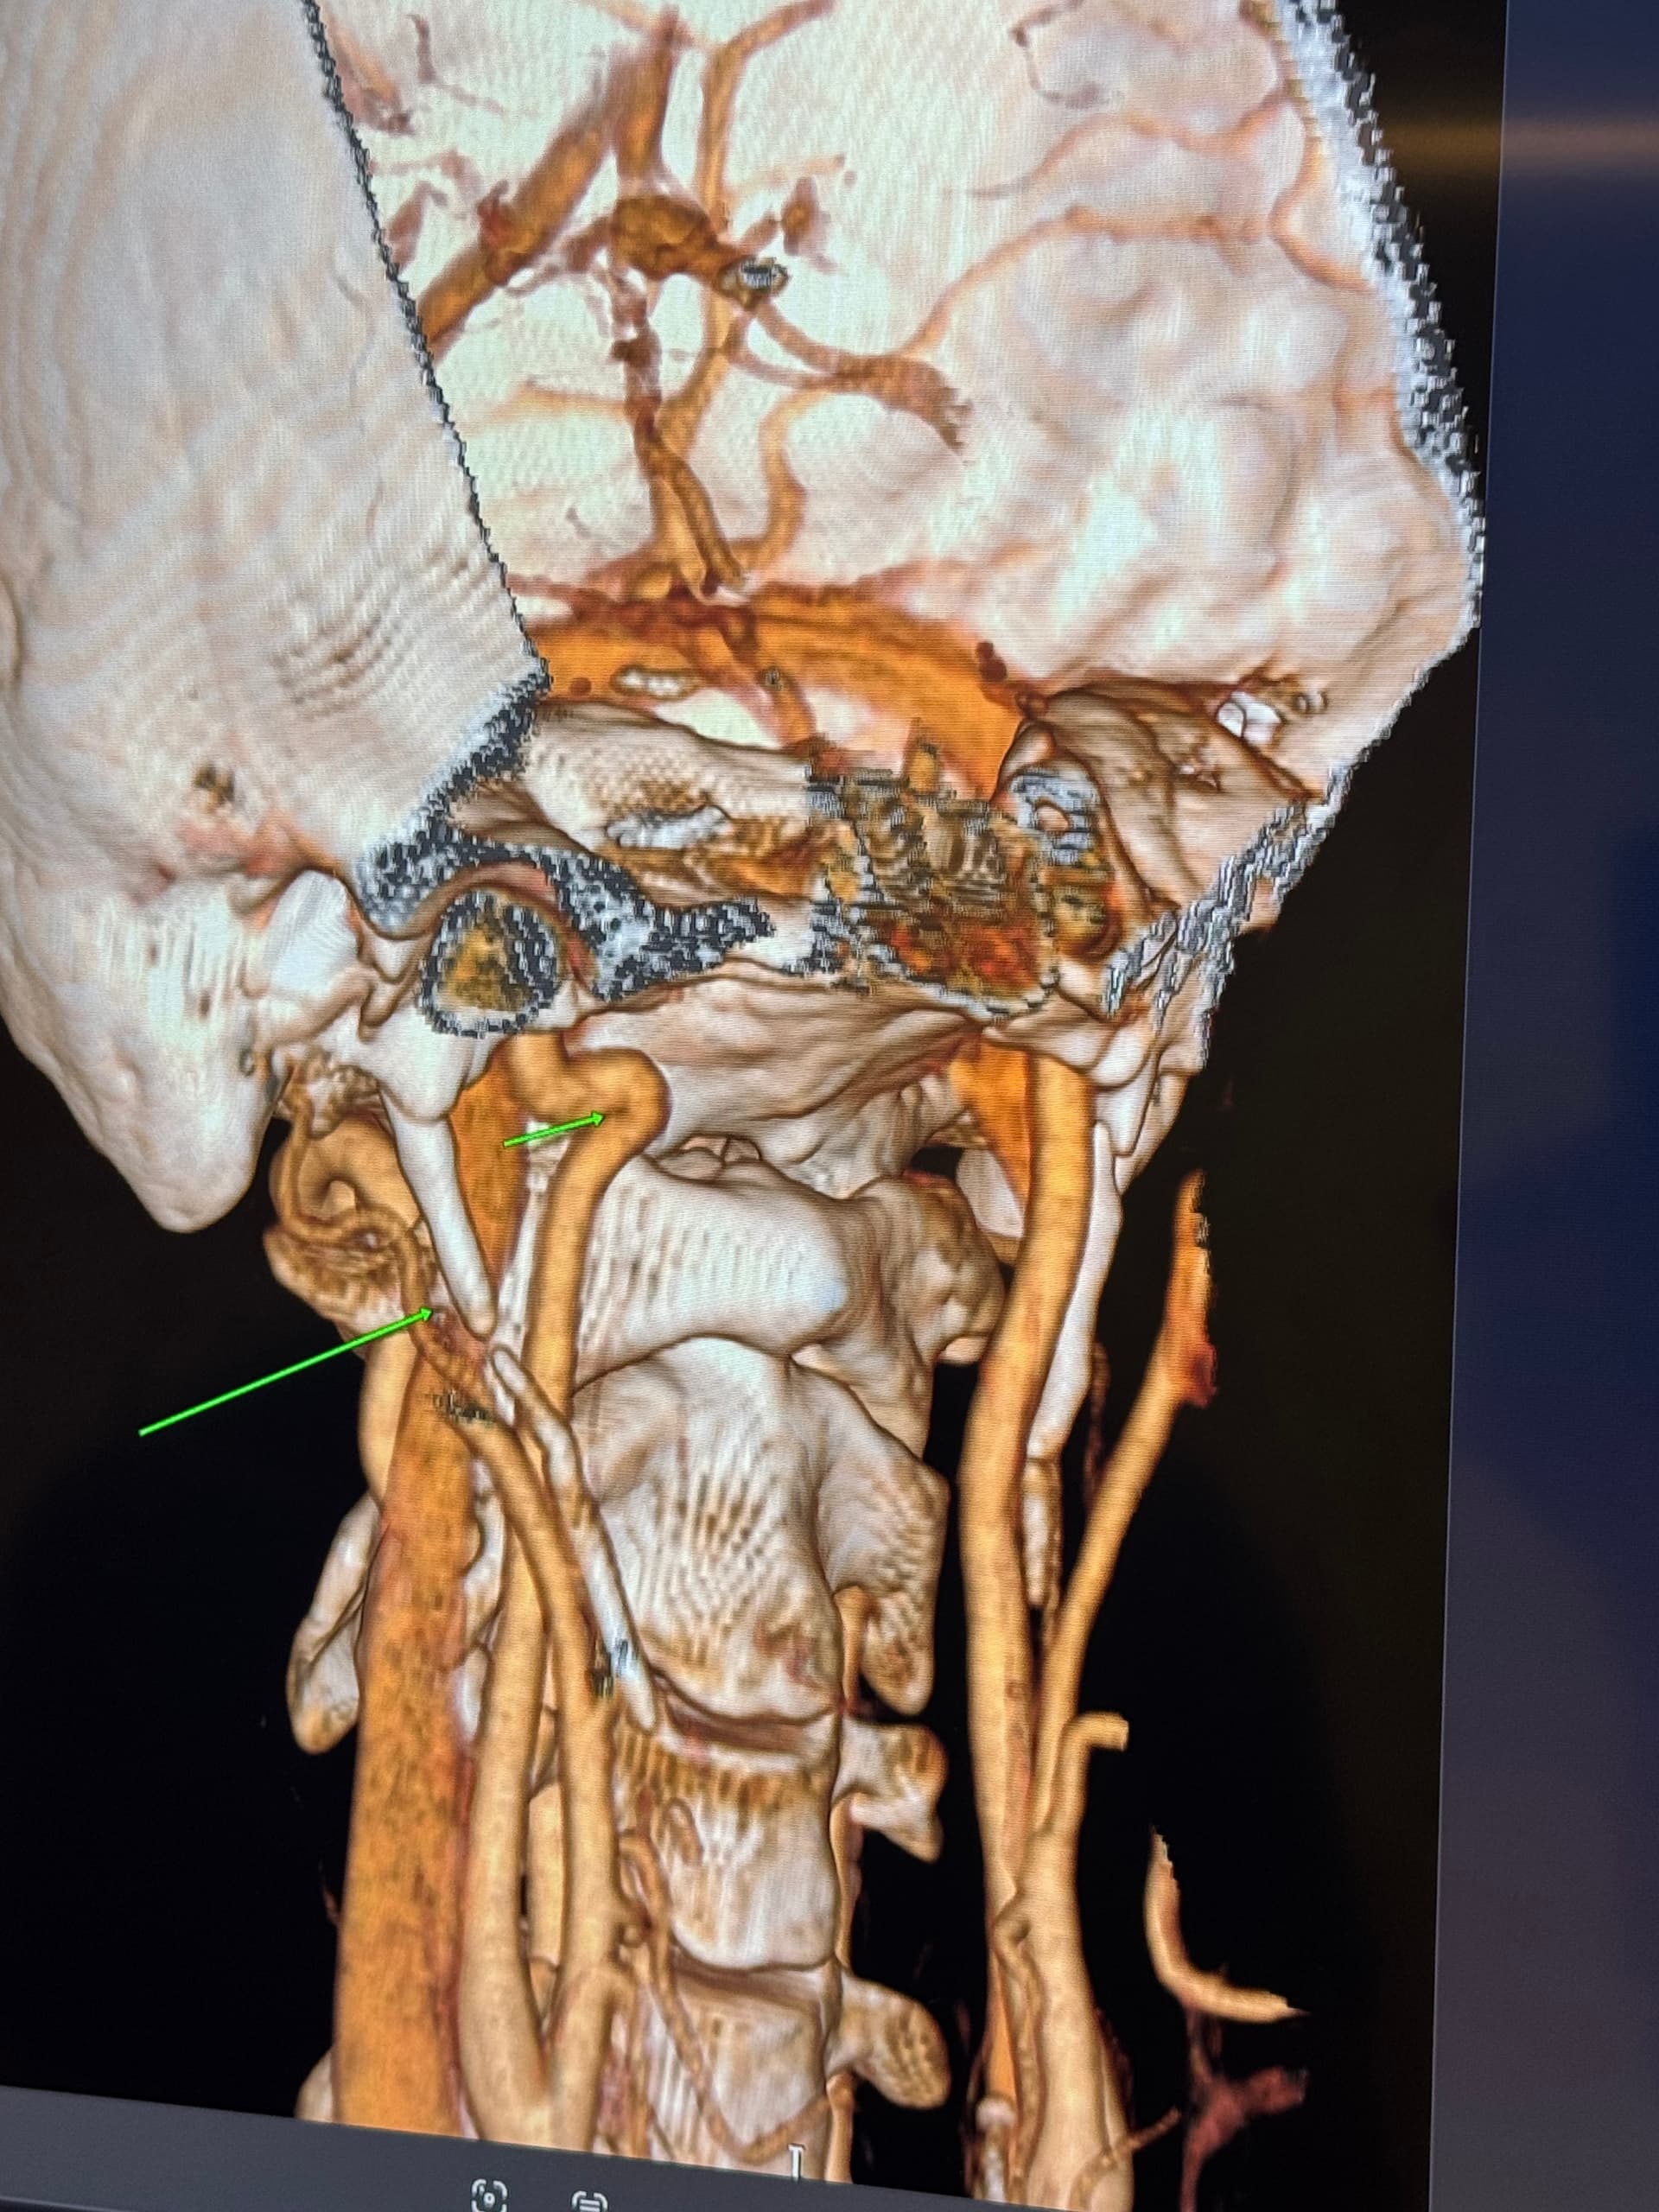

I have a cbct and CVA made wich shows elongated styloids and calcified stylohoids around 5 cm. Space left in neutral position between c1 is 3.5mm. Left IJV compression in laying position but there seems to be mainly some soft tissue compression there. So not due to compression of c1/styloid. The right is my dominant IJV.

They found a kinking carotis artery on the right at the c1 level.

The IJVs do collapse naturally when flat, so it could be due to that, in your 3rd image it looks like the IJV is flattened higher up, so what would be right by the skull base. It could be like that naturally because of being flat for the CT, or it could be that it is being compressed where it emerges from the skull at the jugular foramen - if styloids are quite thick that is possible, & yours do look a little wide at the top… It looks like there could be something pinching the IJV between it & the styloid where you’ve marked too; we’ve had members who’ve had compression from an enlarged SCM muscle, the digastric muscle, omahyoid muscle, as well as other blood vessels & nerves… I’d guess where the compression is that the digastric muscle would be the most likely if it was a muscle, or maybe the stylohyoid muscle, although we don’t hear much about that one!

@Rob12345 - Welcome to our forum! I have nothing to add to what @Jules said, but did want to say WOW! You do have very long styloids. The “kink” in your ICA (internal carotid) isn’t really a kink more of a curve, but I can see based on the image, that it could be causing some slowed or backed up blood flow going into your brain. The IJV compression is curious as it appears to be more than the styloid causing the problem but clearly C1 seems not to be involved. I think Jules has made some logical assumptions regarding other possible compression culprits.

Does anybody know if there seems to be indication of enlarged collaterals on my images that take over the function of the compressed ijvs?

@Rob12345 - I can see you have bilateral IJV compression in the images you’ve posted & it’s possible the middle image in your first set of pictures is pointing to collateral veins. I’m not great at identifying collaterals, but I can say for sure your IJVs are being squashed between your styloids & C1.